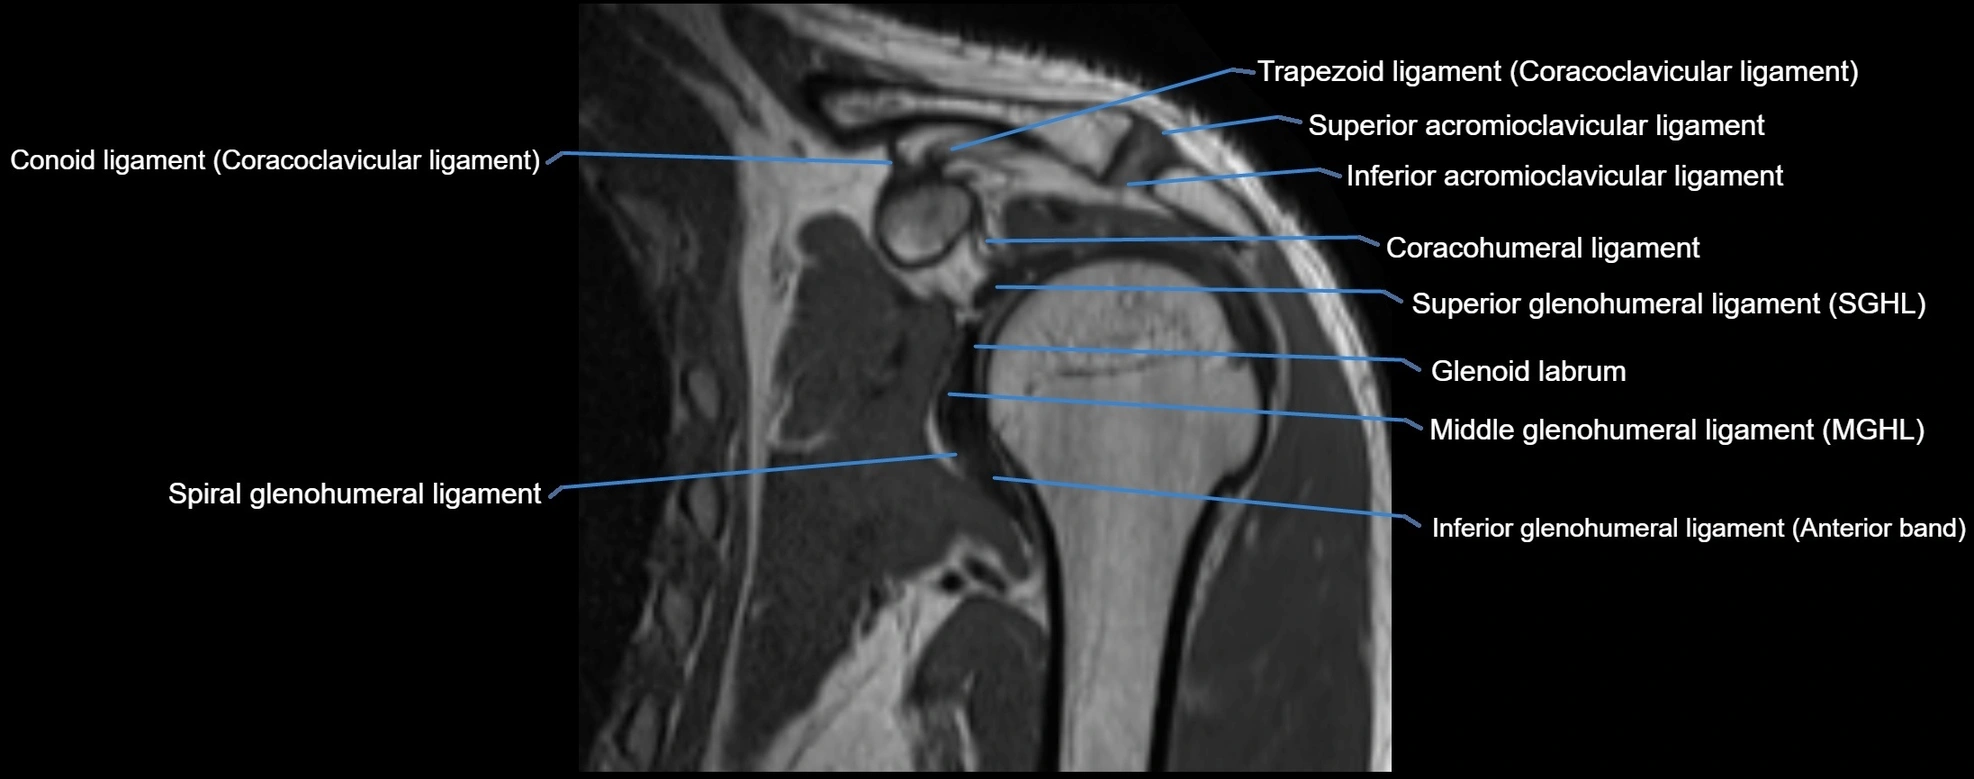

CT image

image